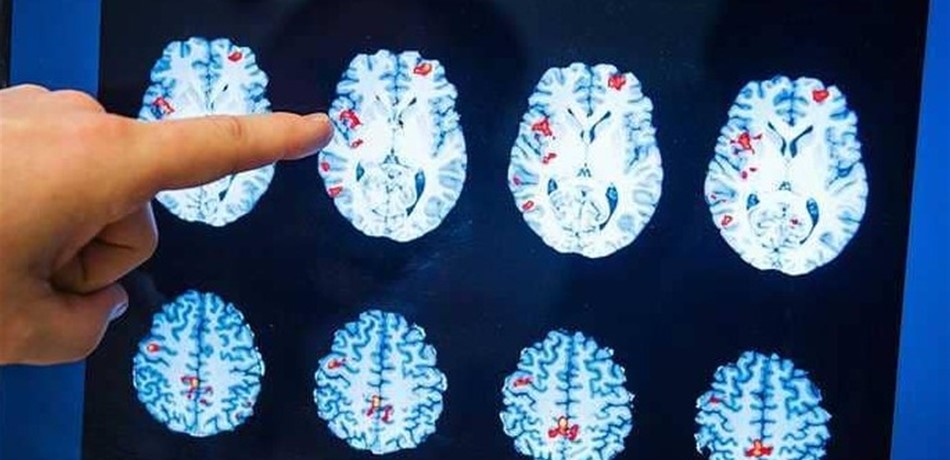

أثارت دراسة جديدة الجدل حول نظريات طال نقاشها من بينها ان الفيروسات التي قد تتسلل إلى المخ قد تلعب دورا في مرض الزهايمر، إلا أنها لا تثبت أن الفيروسات تسبب الزهايمر، كما لا تشير إلى أنه معد.

لكن الفريق الذي يقوده باحثون في مستشفى "ماونت سيناي هيلث سيستم" في نيويورك توصل الى أن فيروسات معينة من بينها هيربس قد يؤثر على سلوك جينات لها علاقة بالزهايمر.

الفكرة هي أن إصابات في وقت مبكر من الحياة قد تهيئ الأوضاع لمرحلة الزهايمر في العقود المتأخرة، برزت داخل الاتجاه العام للطب على مدى سنوات. غير أنه طغى عليها النظرية السائدة بأن الزهايمر ينتج عن تورمات لزجة تسد المخ.

وذكرت دراسة أن بعض المتخصصين حتى ممن لم يؤيدوا صلة العدوى يقولون إنه حان الوقت لإلقاء نظرة فاحصة، ولاسيما أن محاولات عرقلة هذه التورمات التي تسمى باسم تورمات بيتا أميلويد فشلت.